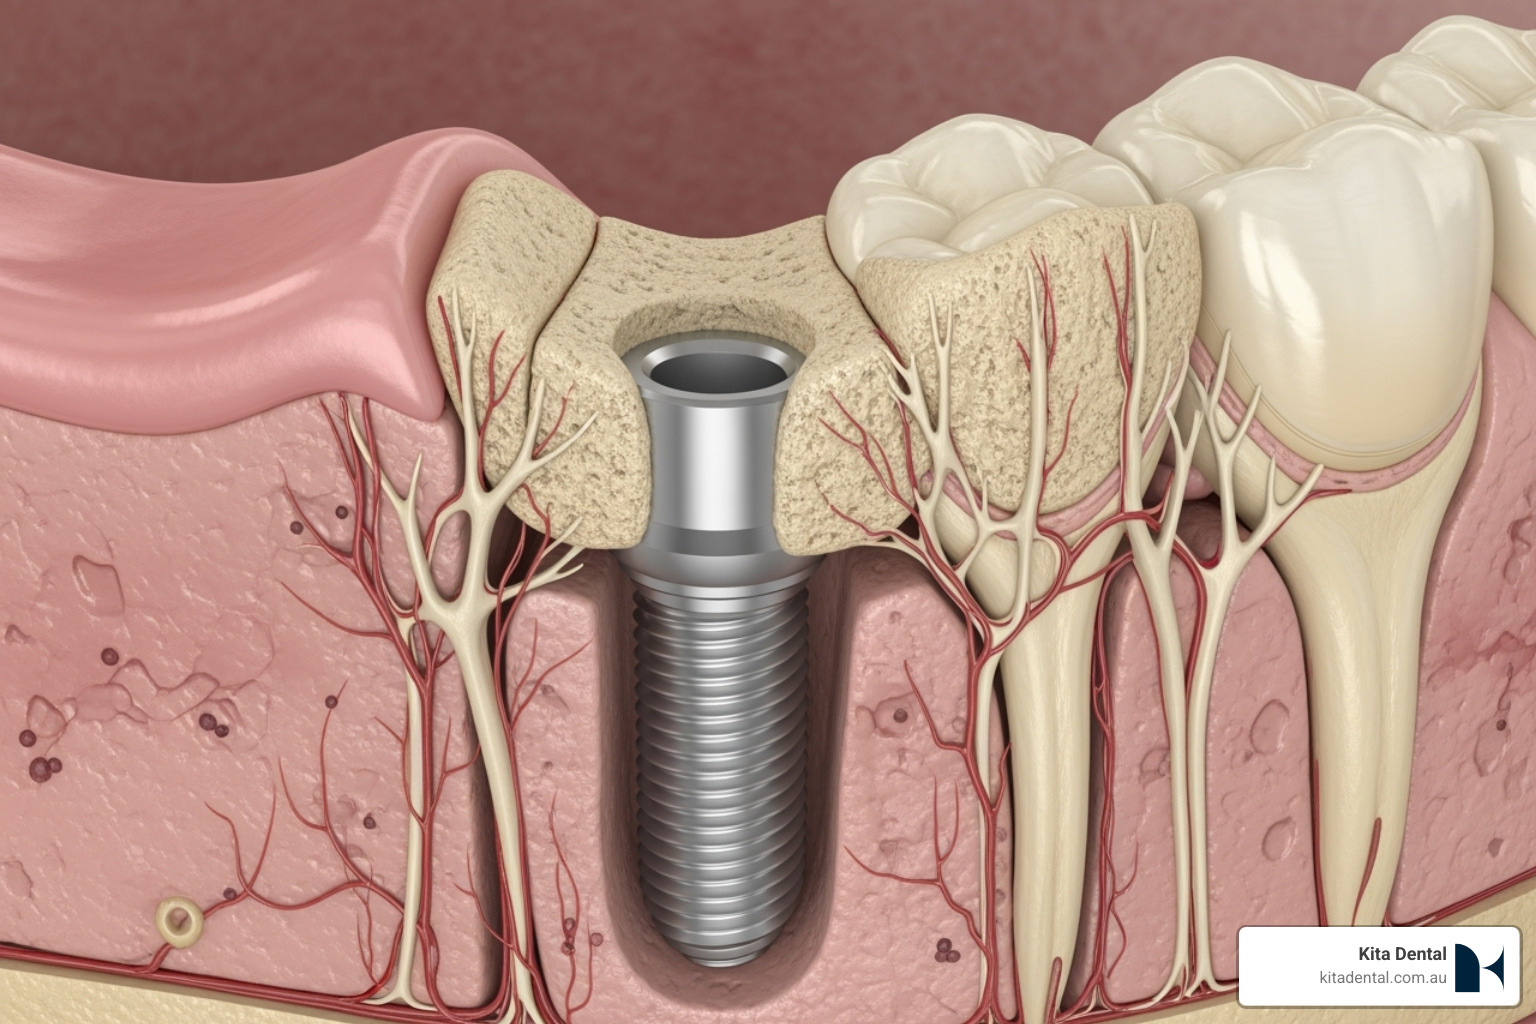

- Implant Placement: A small number of titanium implants are strategically placed in the jawbone to act as strong foundations for your new teeth.

Next is the implant placement surgery. The procedure is performed comfortably under local anaesthetic, and we offer sedation options for anxious patients. We gently place a small number of titanium implants, which will serve as the strong anchors for your new teeth.

Dental implants are small, biocompatible titanium posts that act as an artificial tooth root. Placed in the jawbone, they fuse with the bone through osseointegration, creating a strong foundation for a crown, bridge, or full arch implant restoration. This solution feels natural and restores the ability to eat, speak, and smile with confidence.

- Surgical Placement: We gently place the titanium posts into your jawbone, ensuring your comfort with local anaesthesia and available sedation options.

- Healing Period (Osseointegration): Over a few months, the implant fuses with your jawbone, creating a strong foundation. We can provide temporary restorations during this time.